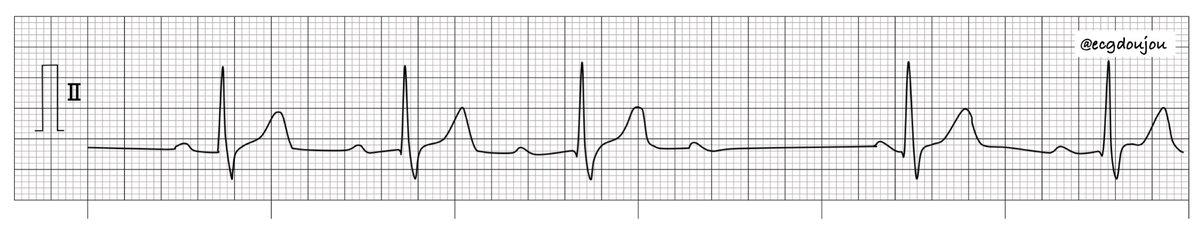

こんばんは👍心電図道場です‼️ 今日も1問心電図です💪 リズムを読んで答えてください🎵

ecgdoujou's tweet image. こんばんは👍心電図道場です‼️

今日も1問心電図です💪

リズムを読んで答えてください🎵